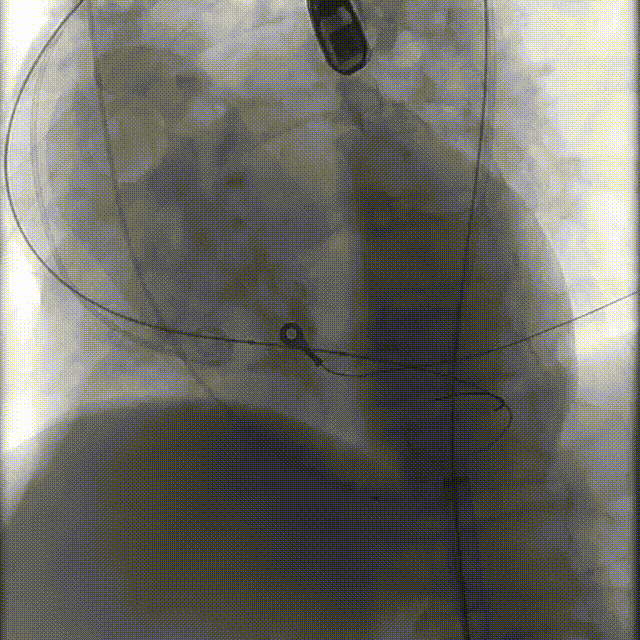

1.经右侧颈内静脉留置临时起搏电极;以左侧股动脉为辅入路,并在造影指导下穿刺右侧股动脉为主入路;

2.主动脉根部造影显示主动脉钙化严重、瓣叶活动度差,伴有轻度反流;

3.直头导丝跨瓣,通过交换导丝将猪尾导管引入左室,测得平均跨瓣压差约77mmHg

4.150次/分快速起搏下以20mm 巴尔特球囊进行预扩张,扩张同时造影无明显腰征,无造影剂反流

5.根据术前评估及球囊预扩情况,选择23mm沛嘉TaurusElite瓣膜进行植入,抓捕器辅助下输送器头端进入左室,零位定位